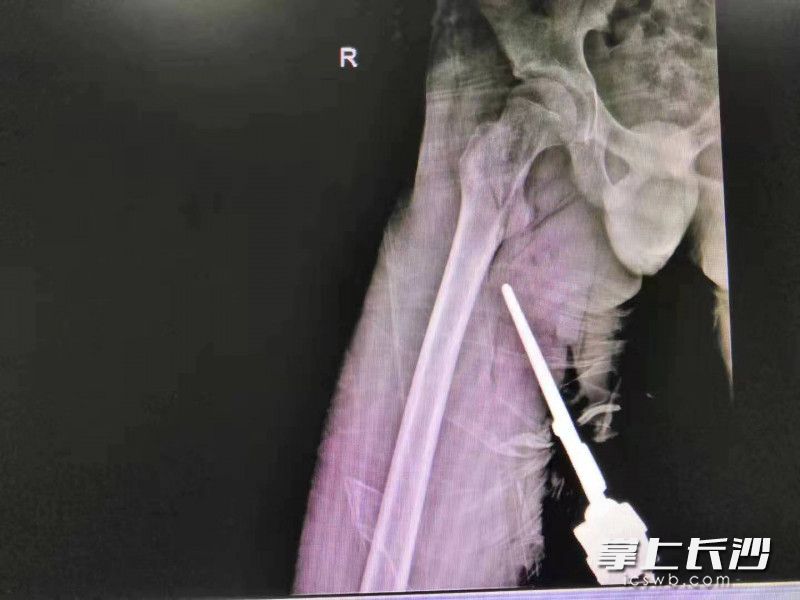

创伤中心副主任医师曾驰在术前通过结合CT影像检查发现外露的金属护栏长约20厘米,其中刺入患者右侧大腿深部的尖端约10厘米,经过精准的血管与神经评估后手术团队开始手术,金属尖端很快被顺利取出。万幸的是,金属尖端虽然导致了小臻的部分肌肉断裂、股动脉及坐骨神经挫伤,但与大腿内的大动脉擦肩而过,没有引发大出血。经过缝合断裂的肌腱,修复撕脱的皮肤软组织后,手术顺利结束。